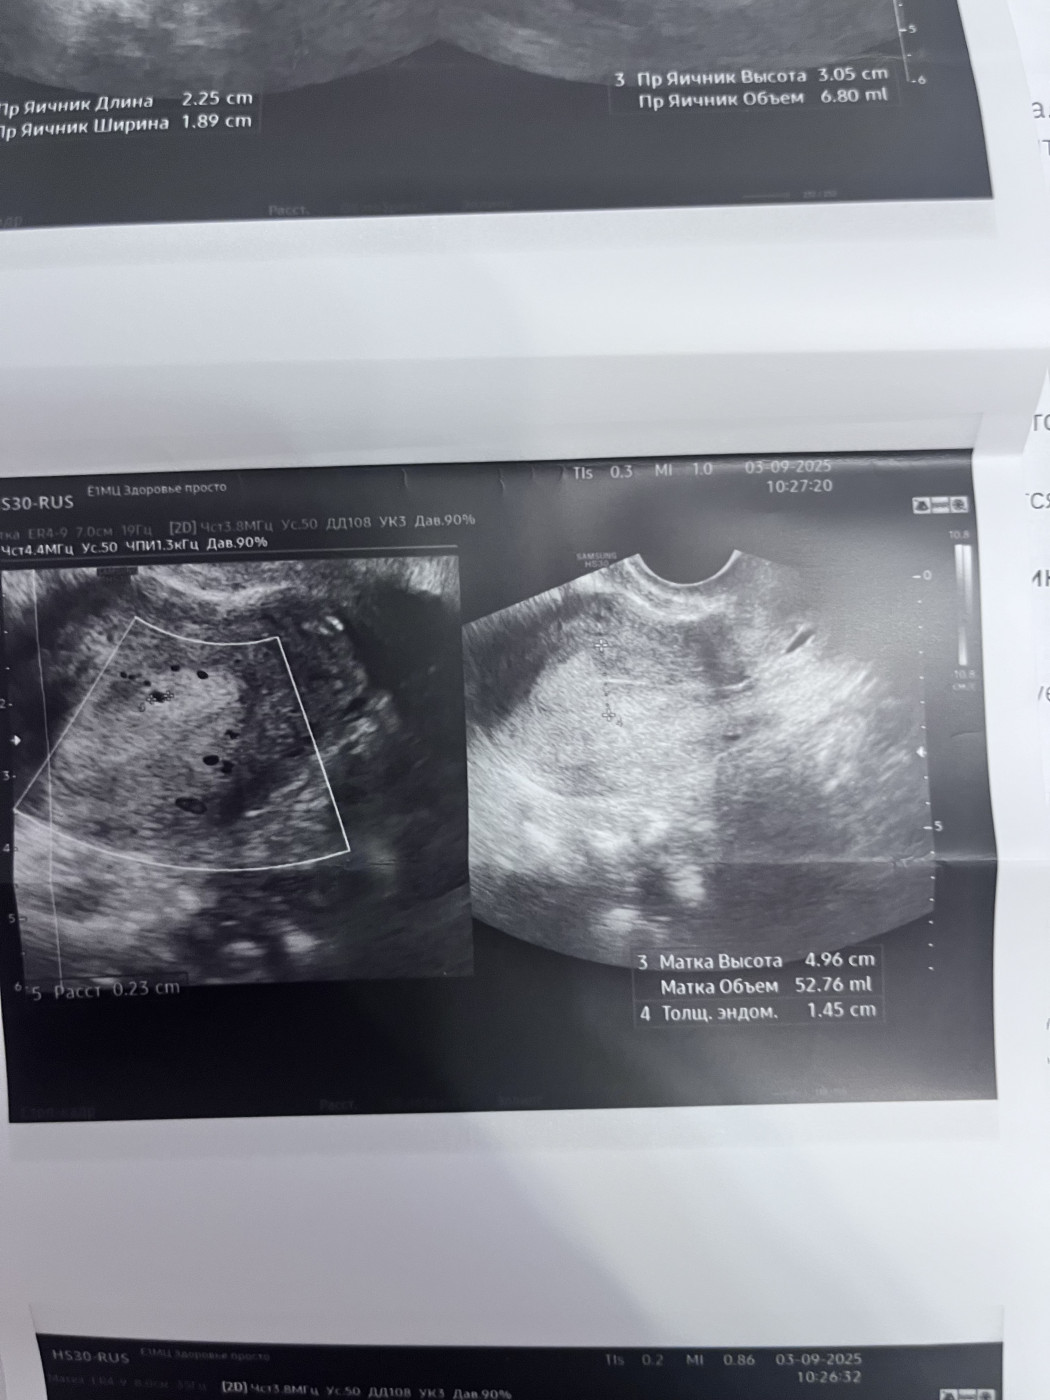

Результаты УЗИ

Поставили диагноз полип эндометрия

Нужна ли гистероскопия с проходимостью труб ?